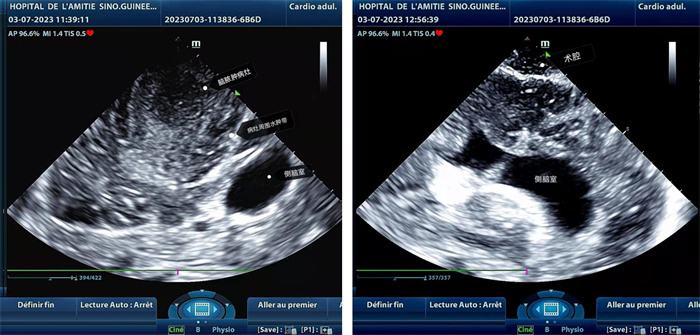

手術(shù)中,張國(guó)濱在超聲科顧秀娟的幫助下,運(yùn)用顱腦術(shù)中超聲技術(shù),通過(guò)將一次性保護(hù)套的超聲探頭置于腦組織表面,實(shí)時(shí)觀察病變的位置和形態(tài),進(jìn)一步確認(rèn)最佳手術(shù)路徑。術(shù)中超聲顯示,病變位于左額頂葉,大小約為4x4x3cm,邊界清晰,呈囊實(shí)性,周邊腦組織水腫明顯。最終,病灶順利切除,診斷為腦膿腫,并通過(guò)超聲檢測(cè)確認(rèn)術(shù)腔無(wú)病變殘留、無(wú)出血,為患者術(shù)后恢復(fù)提供了良好的保障。

左圖顯示術(shù)中超聲見(jiàn)囊實(shí)性病變,大小約為4x4x3cm,病灶周?chē)X組織水腫明顯;右圖為病灶切除后,術(shù)中超聲示術(shù)腔無(wú)病變殘留。中國(guó)第二十九批援幾內(nèi)亞醫(yī)療隊(duì)供圖